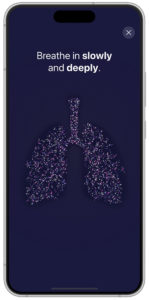

Feedback is simultaneously visualised within the new PARI Breath Guide app, which, as an optional feature, is connected to the eFlow Integrated nebuliser via Bluetooth. The visualised breath guiding feature trains a slow, controlled inspiration. The app uses transferred data to provide real-time feedback and a helpful visualisation of inhalation. This can guide the user to inhale slowly and deeply, which, in turn, can increase the I:E ratio and lead to shorter nebulisation times. Such feedback also informs the patient that the inhalation manoeuvre has been performed correctly (Figure 3).

Figure 3: Visualisation of breath guiding in app (prototype).

A more detailed inhalation report is given within the app at the end of each therapy to inform patients about their inhalation technique and therefore strengthen their engagement and self-management. This can support patients in their effective inhalation to promote the best possible therapy outcomes. With this new digital feature, PARI sends feedback to guide the patient to an optimal breathing pattern.